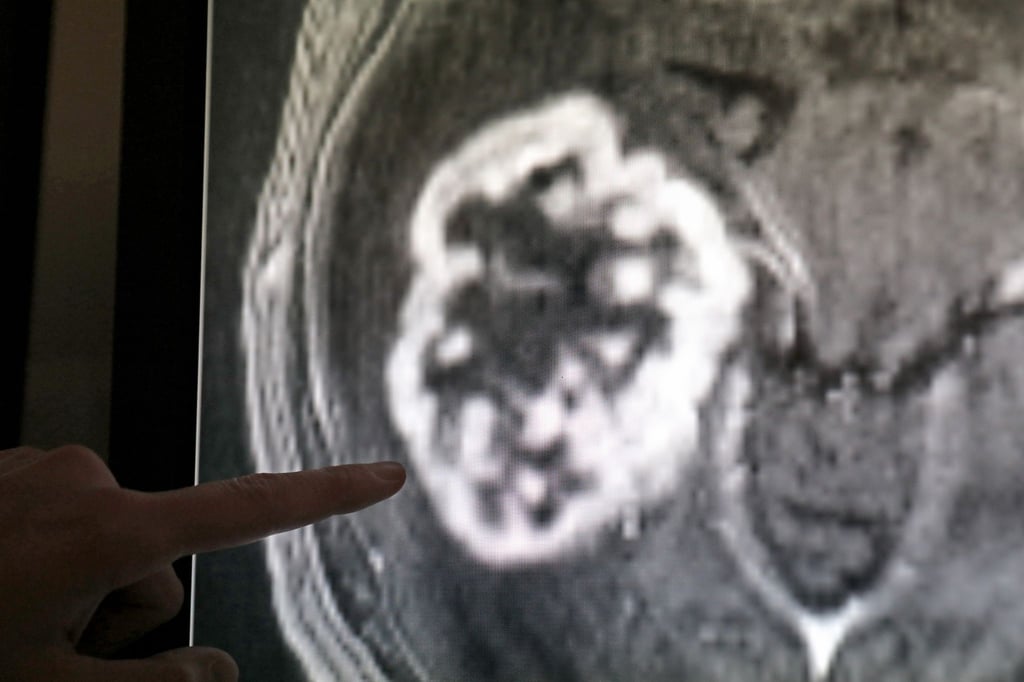

Gesundheit Statistik: Jeder fünfte Todesfall durch Krebs verursacht

Den Weltkrebstag am 4. Februar nutzen Krankenkassen und medizinische Fachgesellschaften zur Aufklärung über Tumorerkrankungen. Wie wichtig das ist, zeigt ein Blick in die Statistik der Todesursachen.

Erfurt - Etwa jeder fünfte Todesfall in Thüringen ist nach statistischen Daten auf Krebs zurückzuführen. Im Jahr 2022 betraf das 6771 der insgesamt 32.795 Sterbefälle, wie das Statistische Landesamt am Freitag in Erfurt mitteilte. Für 3843 Männer und 2928 Frauen verlief eine Krebserkrankung demnach tödlich, wobei die Gestorbenen im Schnitt 78,8 Jahre alt wurden. Sie starben durchschnittlich 4,6 Jahre früher als nicht an Krebs Erkrankte.

Mehr als 10 Prozent der an Krebs Gestorbenen war jünger als 60 Jahre. Rund ein Drittel der tödlich verlaufenen Tumorerkrankungen betraf Krebs der Verdauungsorgane, wozu etwa Speiseröhren- und Darmkrebs zählen.